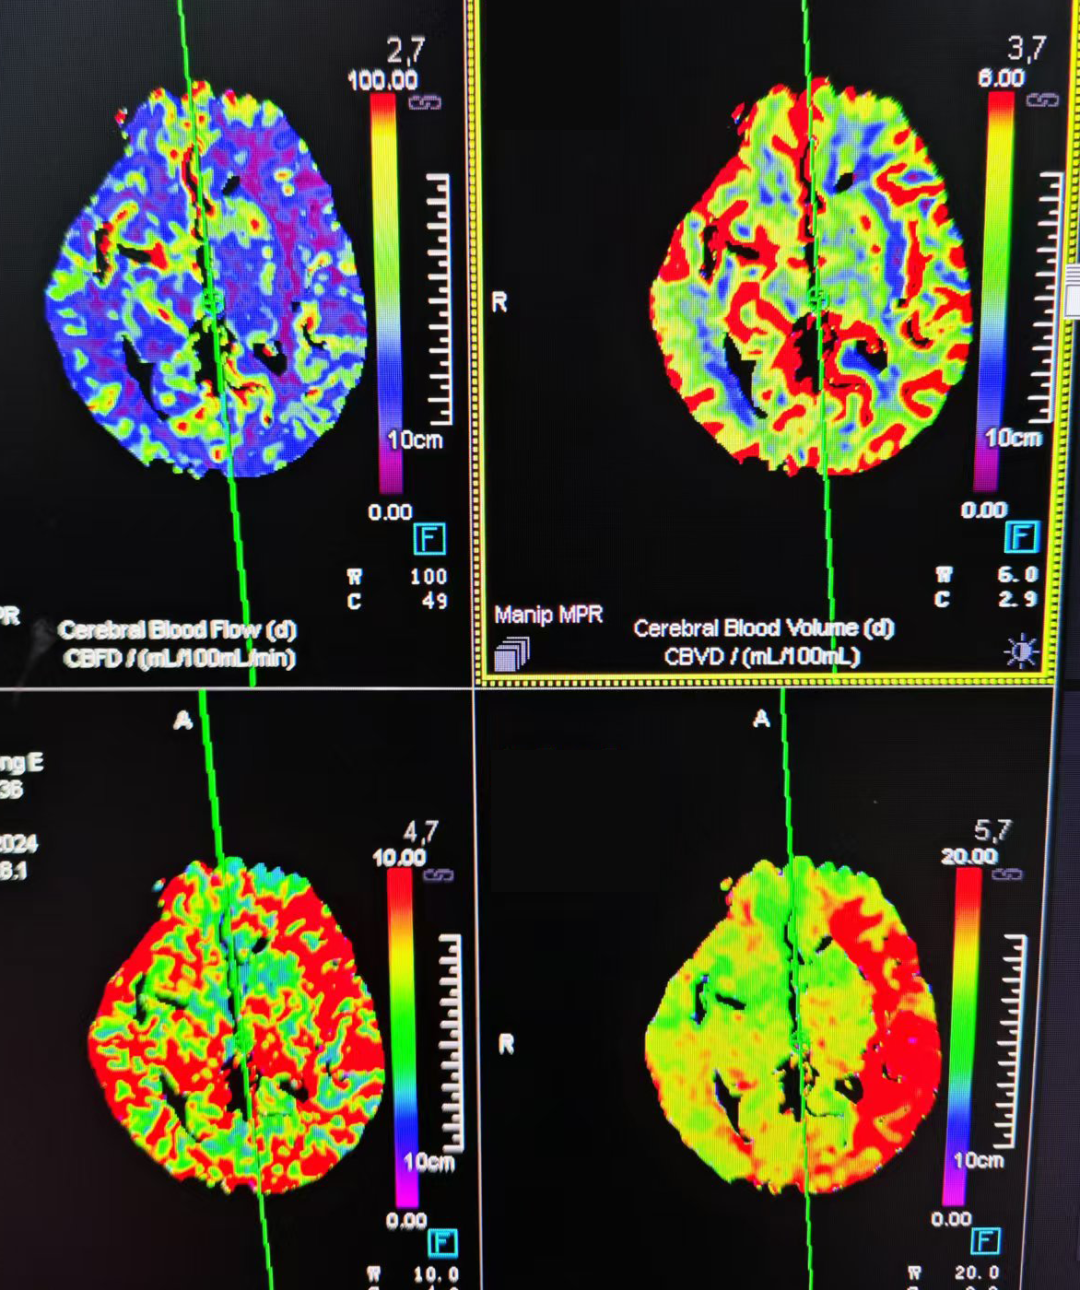

术前CTP提示左侧大脑半球大片低灌注,小核心梗死区。

动脉长鞘怎么置入有励可说|Locaste 088励楷长鞘及Tarvos微导丝在左侧大脑中动脉闭塞取栓术中的应用_https://www.jmylbn.com_新闻资讯_第6张

动脉长鞘怎么置入有励可说|Locaste 088励楷长鞘及Tarvos微导丝在左侧大脑中动脉闭塞取栓术中的应用_https://www.jmylbn.com_新闻资讯_第7张